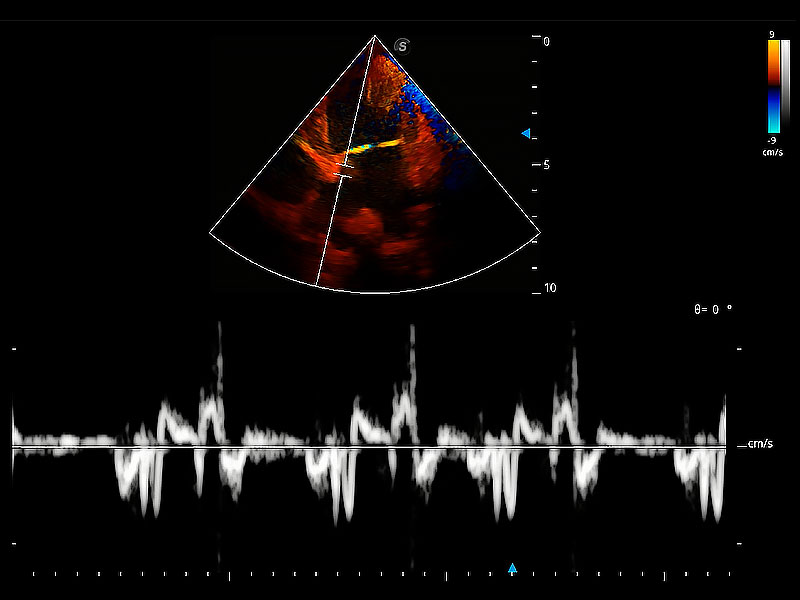

实时用颜色表示心肌组织运动,观察和定量组织的运动情況,对快速检测与评估心肌的灌注和活性、电传导及心肌收缩和舒张功能等均能提供重要的诊断信息。